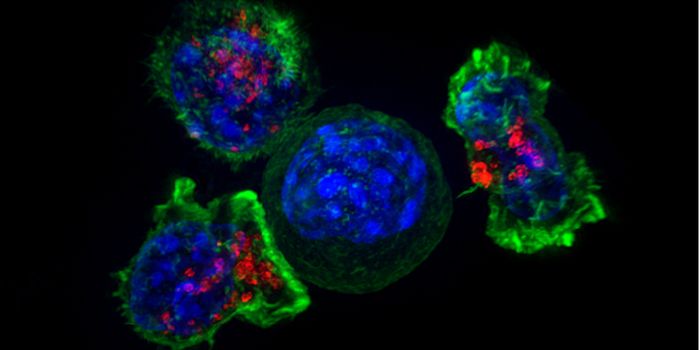

MAY 13, 2021ImmunologyThe immune system is programmed to recognize foreign bodies as potentially dangerous, promptly removing them before the ...

MAR 18, 2021Drug Discovery & DevelopmentResearchers have developed a prototype for a new kind of cancer immunotherapy. The therapy uses engineered T-cells to ta ...